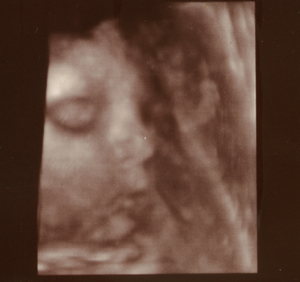

Nagyon édesek a bébik!!!

Kriszti: a középső képre akartam neked írni, hogy tiszta Levente, mikor rájöttem, hogy naná, hogy tiszta levenet

. Nagyon édes!!! Még szép, hogy édes mivel Levente!